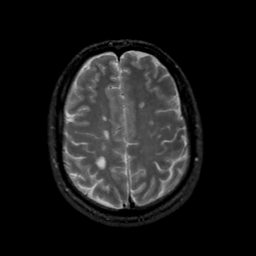

MR Study #18, July 21, 1991 -- Slice #37

[Home][Help][Clinical][Tour 1][Tour 2] Slice 37